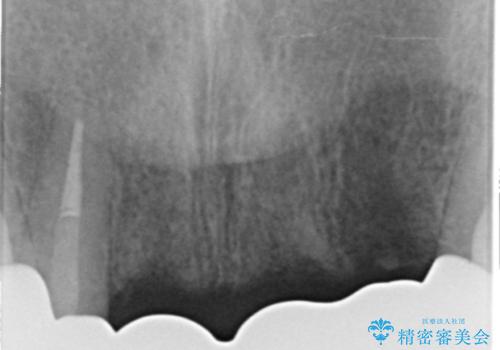

精査したところ、左上の側切歯(左上2)も破折しており保存不可能な状態でした。

左上の側切歯(左上2)を抜去し、右上の側切歯(右上2)の再根管治療後、セラミックのブリッジによる補綴を行いました。